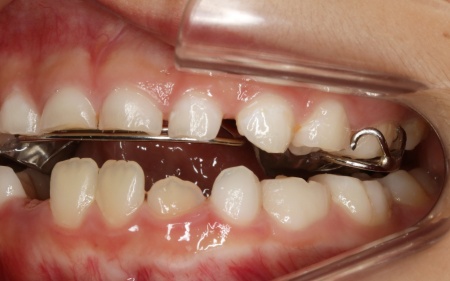

治療前

診断結果 拝見したところ、患者様は乳歯のみが生えている乳歯列期の段階でしたが、この時点ですでに反対咬合が認められました。

反対咬合とは、下の前歯が上の前歯よりも前に出ている状態のことで、一般的に「受け口」とも呼ばれます。